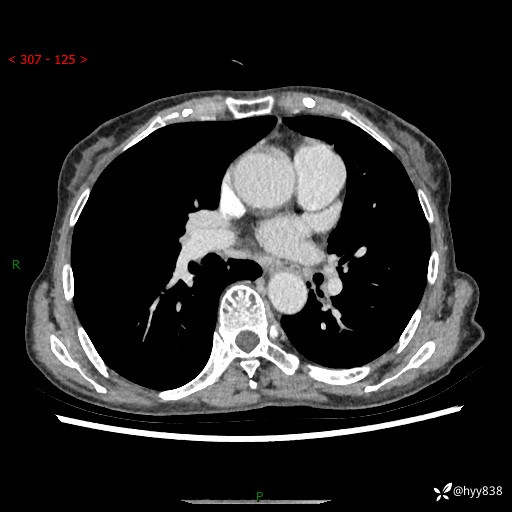

胸部CT平扫+增强